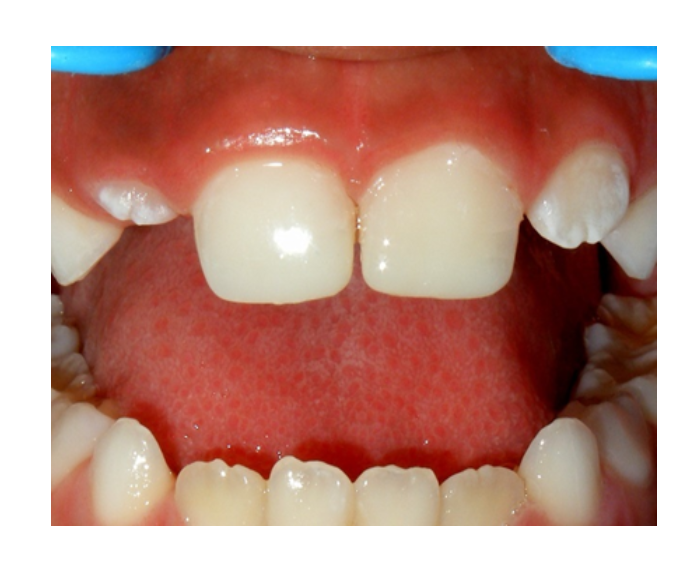

Mordida Cruzada anterior unidental